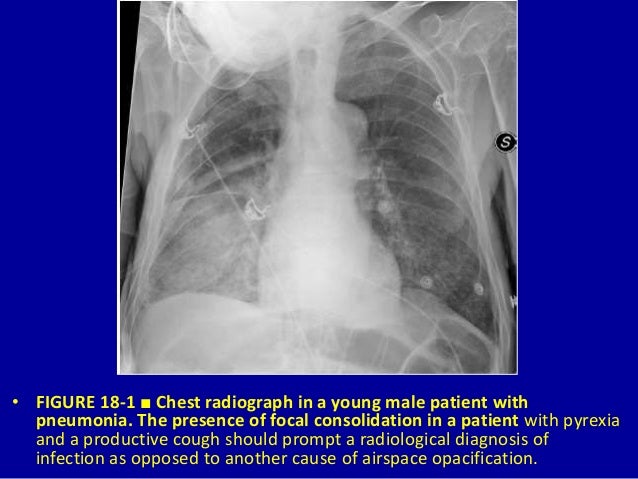

18 Airspace Diseases Dr Muhammad Bin Zulfiqar